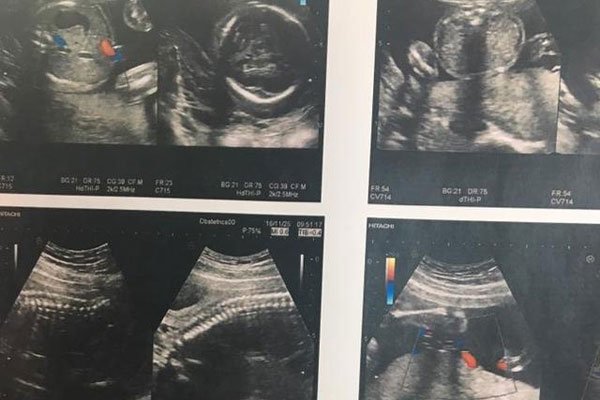

无法判定孩子性别的时候,一些人就会把十男九漏这种事情当做判定自己生的是不是男孩儿的标准,其实从医学的角度来看,根本不存在所谓的十男九漏,一般来说十男九漏的现象会发生在孕早期,早期孕妇出血分多种情况,如果出血的血液,呈现出咖啡色,那么就没什么事情,不用太过担心,这只是氧化的缘故,说明出血已经停止,只要多注意休息,不要过度运动就可以了。

但是如果孕妇出血一直都是鲜红色的,那么一定要注意了,会发生这种情况一般是因为怀孕初期胚胎着床不稳定,出现这种情况并不代表是流产,只能说流产的几率比较大。第二种可能性是宫外孕,孕妇在6-7周时,用超声波还未看到胚胎,但是却有出血的症状,并且人类绒毛膜激素偏高时,这很可能就是宫外孕的情况,孕妈妈要注意伴随出血的同时是否有下腹疼痛的情况发生,有的话要立即就医。